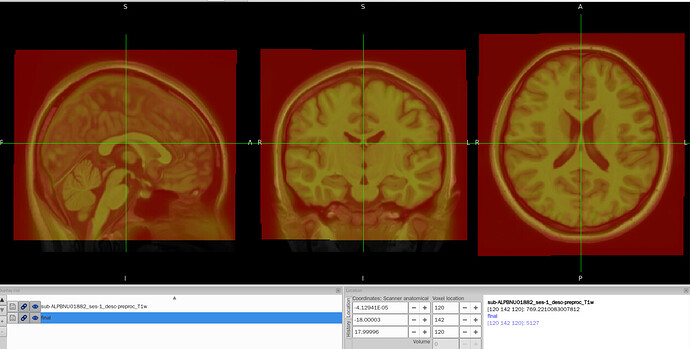

I tried to convert the ANTs-format warp (from-MNI152NLin2009cAsym_to-T1w_mode-image_xfm.h5) generated by fMRIPrep into FSL format (from-MNI152NLin2009cAsym_to-T1w_mode-image_xfm_fsl.nii.gz) using c3d affine tool, so that I could use it later in pyAFQ for tractography. The conversion itself works fine, but once I add intent code to FSL xfm header(intent code 2006), the warp seems to be damaged. To be specific, the FSL warp applied to MNI template shifted to the lower-left corner and it no longer aligns with the T1w image.